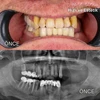

Implant tedavisi